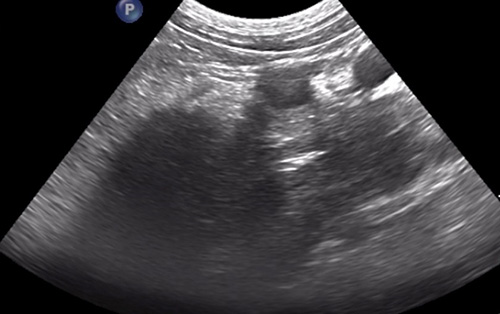

“When we performed a focal ultrasound of the area, we also found a foreign body (suspected to be a grass seed) at the very end of the abscess, close to the main vessels of the abdomen.

“Our anaesthesia team made a plan for a safe and long anaesthetic, two surgeons prepared for his exploratory sternotomy and laparotomy, and colleagues from diagnostic imaging came into theatre to help us localise the foreign body safely with ultrasound.

“The ultrasound meant we could see the foreign body which helped target the area and minimise surgical exploration in a very tricky spot, where some of the main abdominal vessels are situated.